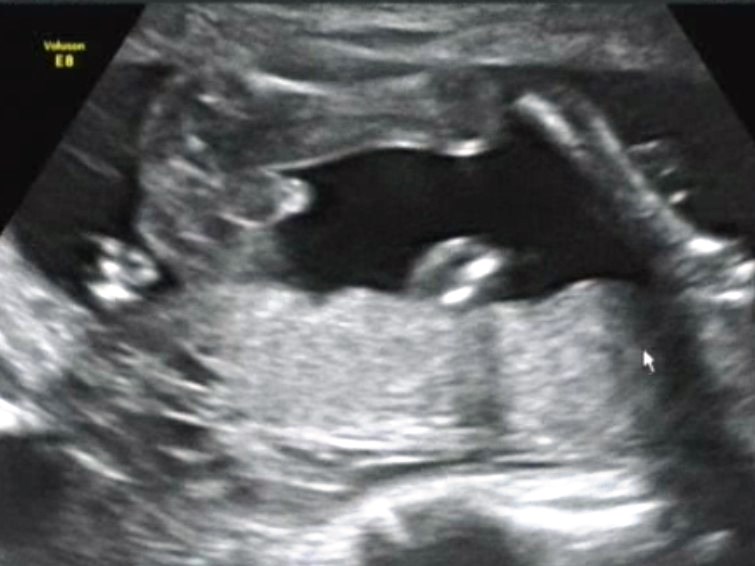

На УЗИ скрининг пошли с мужем в 20+1, первый мой вопрос был конечно про пол)) В общем поводив датчиком сказали что это мальчуган и показали такое:

Наверное, такое не отвалится :DDD В общем наш бугорок, который в 12 недель был аккурат параллельно позвоночнику (как у девочек) превратился через 2 месяца в мошонку и крантик. Муж был рад, как никогда - всегда мечтал о лего- радиоуправляемых вертолетиках-железной дороге-машинках СЫНЕ